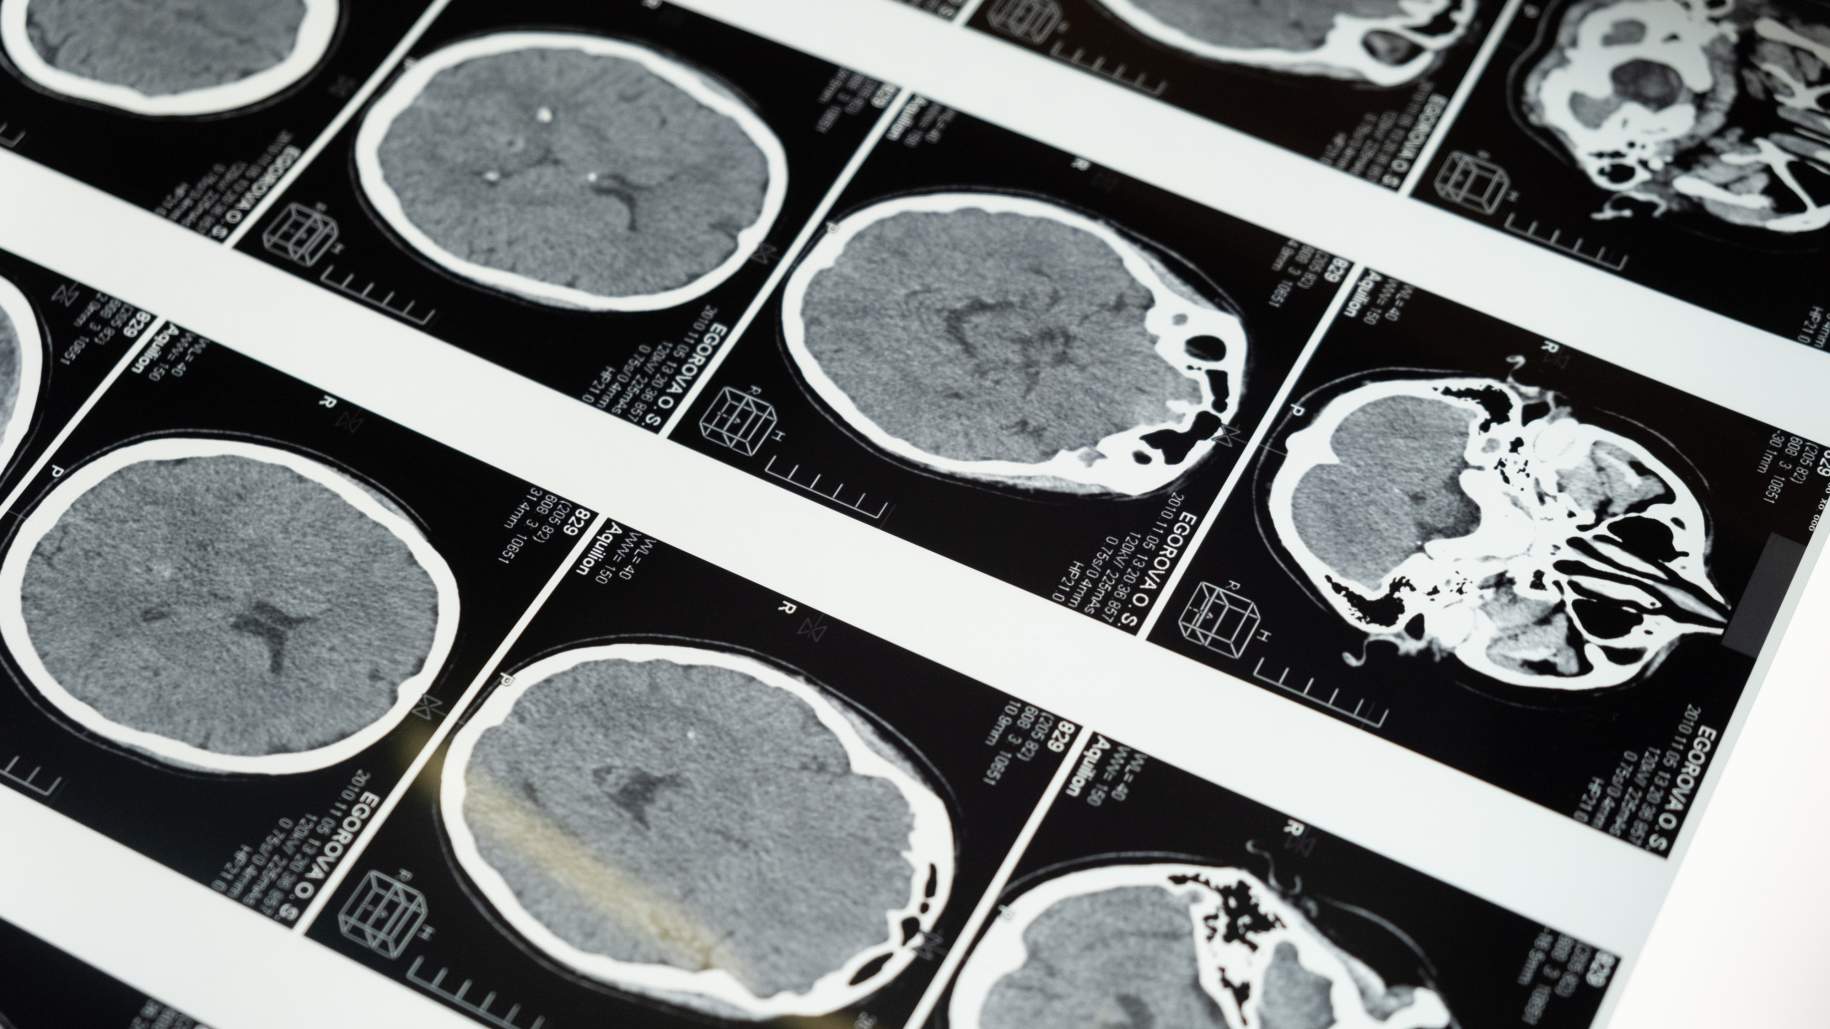

Si se le considera un buen candidato para la cirugía, su cirujano creará un plan quirúrgico. Esto a menudo implica diagnóstico por imágenes, como una resonancia magnética o una tomografía computarizada, para localizar la posición exacta del tumor dentro del cráneo. En algunos casos raros, se puede realizar una angiografía para estudiar los vasos sanguíneos que van al tumor. Una angiografía es una técnica de imágenes que se puede utilizar para mapear los diferentes vasos sanguíneos que suministran oxígeno y nutrientes al meningioma.